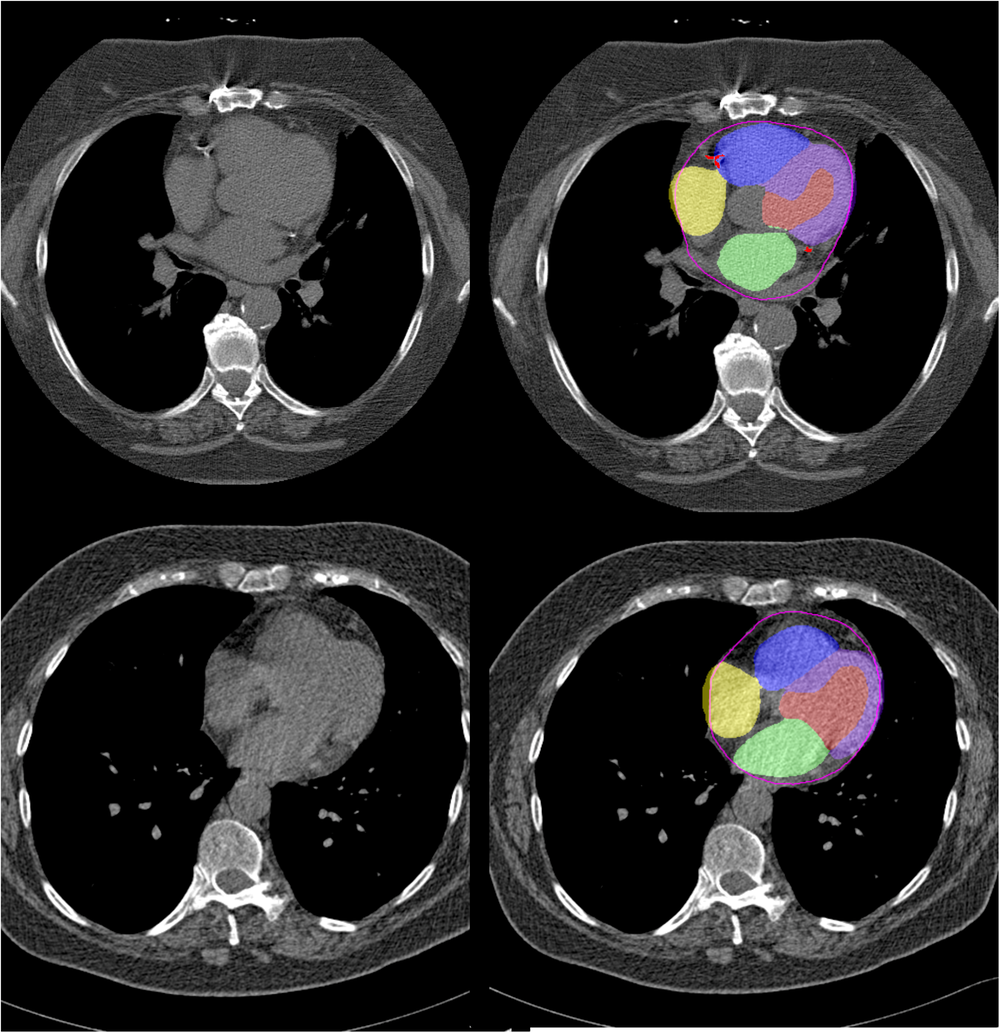

Fig. 3: Case examples.

Representative non-contrast computed tomography slices for two patients (left), with super-imposed segmentations (right). One artificial intelligence (AI) model was used to segment a cardiac mask (magenta line) and coronary artery calcium (red). A second AI model segmented left ventricular myocardium (purple), left atrial (green), left ventricle (light red), right ventricle (blue) and right atrial (yellow) volumes.